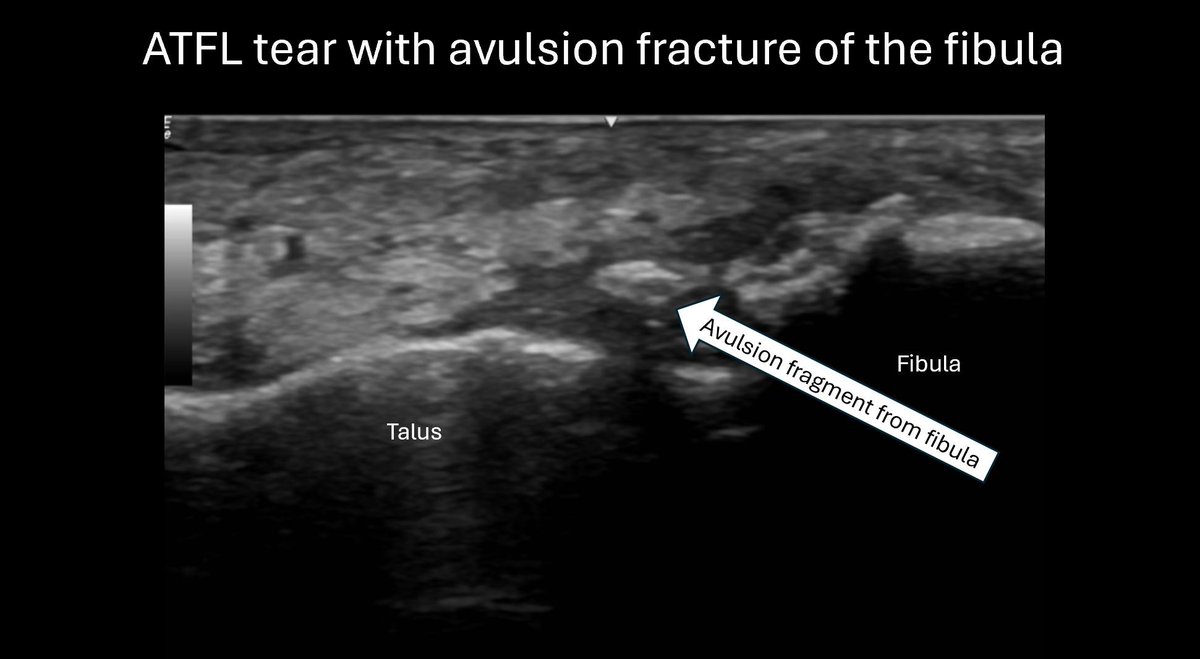

When hunting for an avulsion fracture one hint is the presence of a nice big bruise! Bone is highly vascular and so bleeds when injured, If you see an swollen and bruised lateral ankle sprain go hunting for an avulsion!! #diagnosticultrasound #highanklesprain #anklepain #sprain